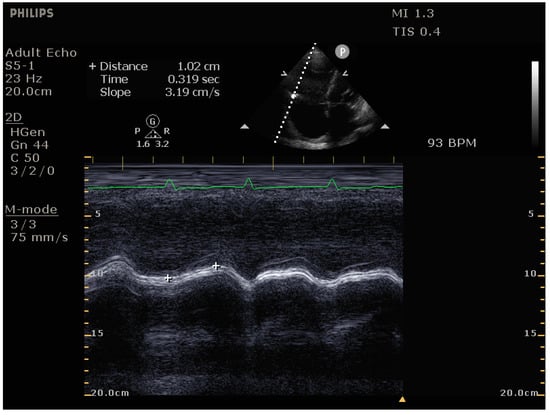

- Signs of impaired RV systolic function: reduced tricuspid annular plane systolic excursion (TAPSE)